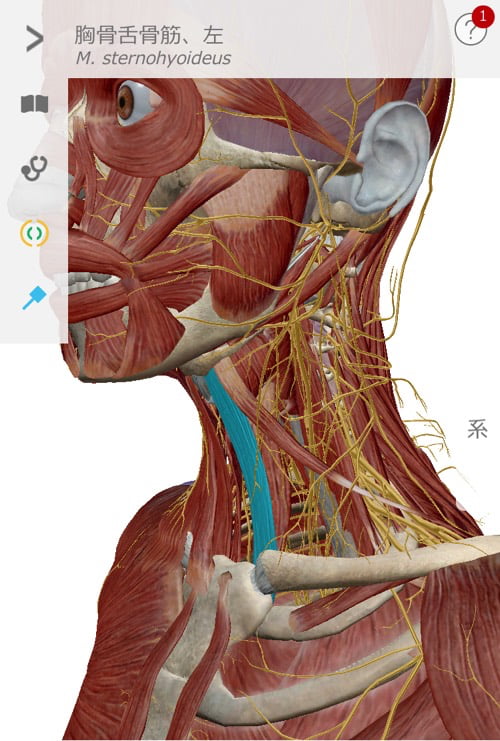

顎下から鎖骨、そして肘に向かうラインに硬直やヨジレが集中しています。

次に顎周りを緩めて首周りの硬直とズレをなくします。

そして四十肩に大きく関連している鎖骨周りを調整。

最後に張りが残っていた首後ろの深層部を調えて施術は終了です。